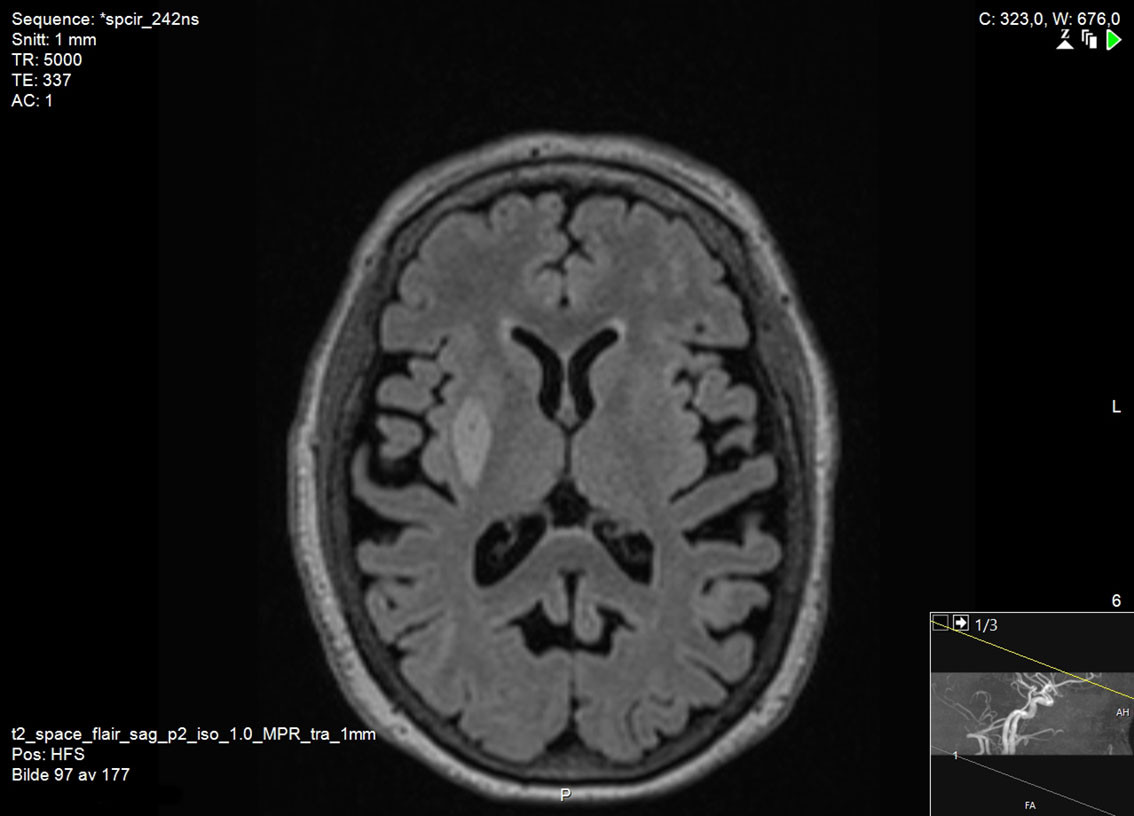

Det er ingen allment vedtatte retningslinjer for diagnostisk avklaring av vaskulær parkinsonisme, men basert på kliniske funn og patologi har Zijlmans og medarbeidere foreslått følgende kriterier: a) parkinsonisme, b) cerebrovaskulær sykdom påvist ved MR eller CT og c) en sammenheng mellom a) og b), enten i form av akutt hemiparkinsonisme fra infarkt eller blødning i den nigrostriatale banen (subtype 1) eller småkarsykdom i hvit substans med en gradvis utvikling av parkinsonisme (subtype 2) (15). Som regel er MR av hjernen nødvendig for å avgjøre om det foreligger skade i den nigrostriatale banen (figur 1) eller småkarsykdom i hvit substans (figur 2). CT av hjernen er mindre egnet for å stille diagnosen på grunn av lavere sensitivitet for lakunære infarkter og småkarsykdom (5).